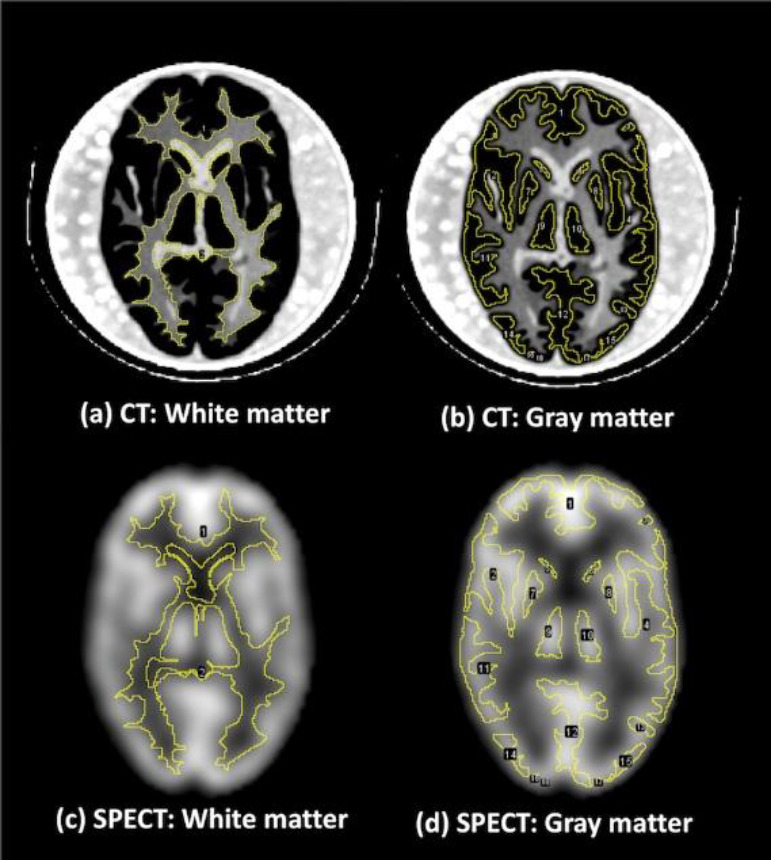

Methods: SPECT images of the brain phantom were acquired from eight devices in five institutions. The phantom was filled with 28 kBq/ml of 99mTc solution at the start of scanning. We obtained various data with different acquisition times under clinical reconstruction and acquisition conditions at each institution. Four physical parameters (percent contrast, contrast noise ratio (CNR), asymmetry index (AI), and sharpness index (SI)) were measured with the phantom. Seven observers blindly evaluated all image series and scored them on a scale of 1-3 using four checkpoints: contrast, image noise, symmetry, and sharpness. The average score for all observers was calculated.